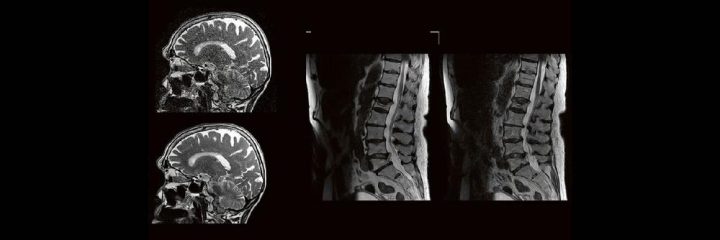

Dr. med. André ReisbergDr. med Sebastian Plößl Die bildgebende HNO-Diagnostik macht es Anfängern nicht leicht. Die Anatomie ist komplex und weniger intuitiv als in anderen Körperregionen. Normvarianten erschweren insbesondere in den Nasennebenhöhlen den Lernprozess. Sobald pathophysiologische Zusammenhänge verstanden und wichtige klinische Aspekte verinnerlicht wurden, gelingt es einen praxistauglichen, belastbaren Befund zu erstellen. Wo muss ich eigentlich hinschauen? Was will der Kliniker von mir wissen und warum? Begleiten Sie uns auf einer kooperativen Reise durch die NNH mit „Ach so!“-Garantie: GemeinsamWeiterlesen